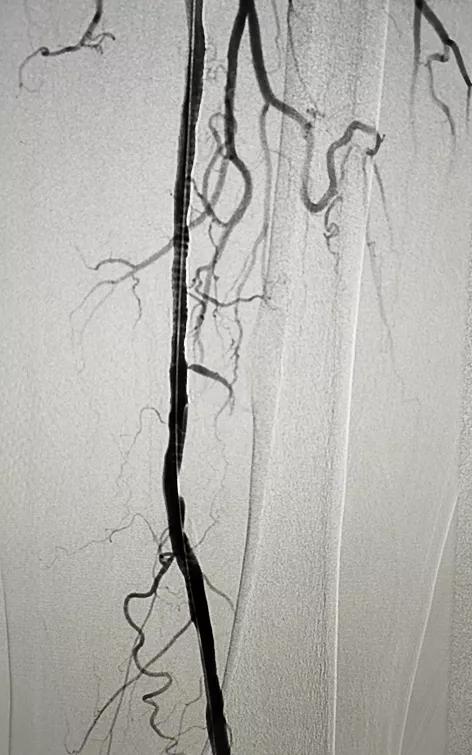

术后造影显示支架内血流通畅,狭窄消失,患者安返病房。术后第二天,唐大叔就下地行走,胫后动脉搏动良好,左下肢肌力及肌张力正常。

术后造影显示狭窄消失